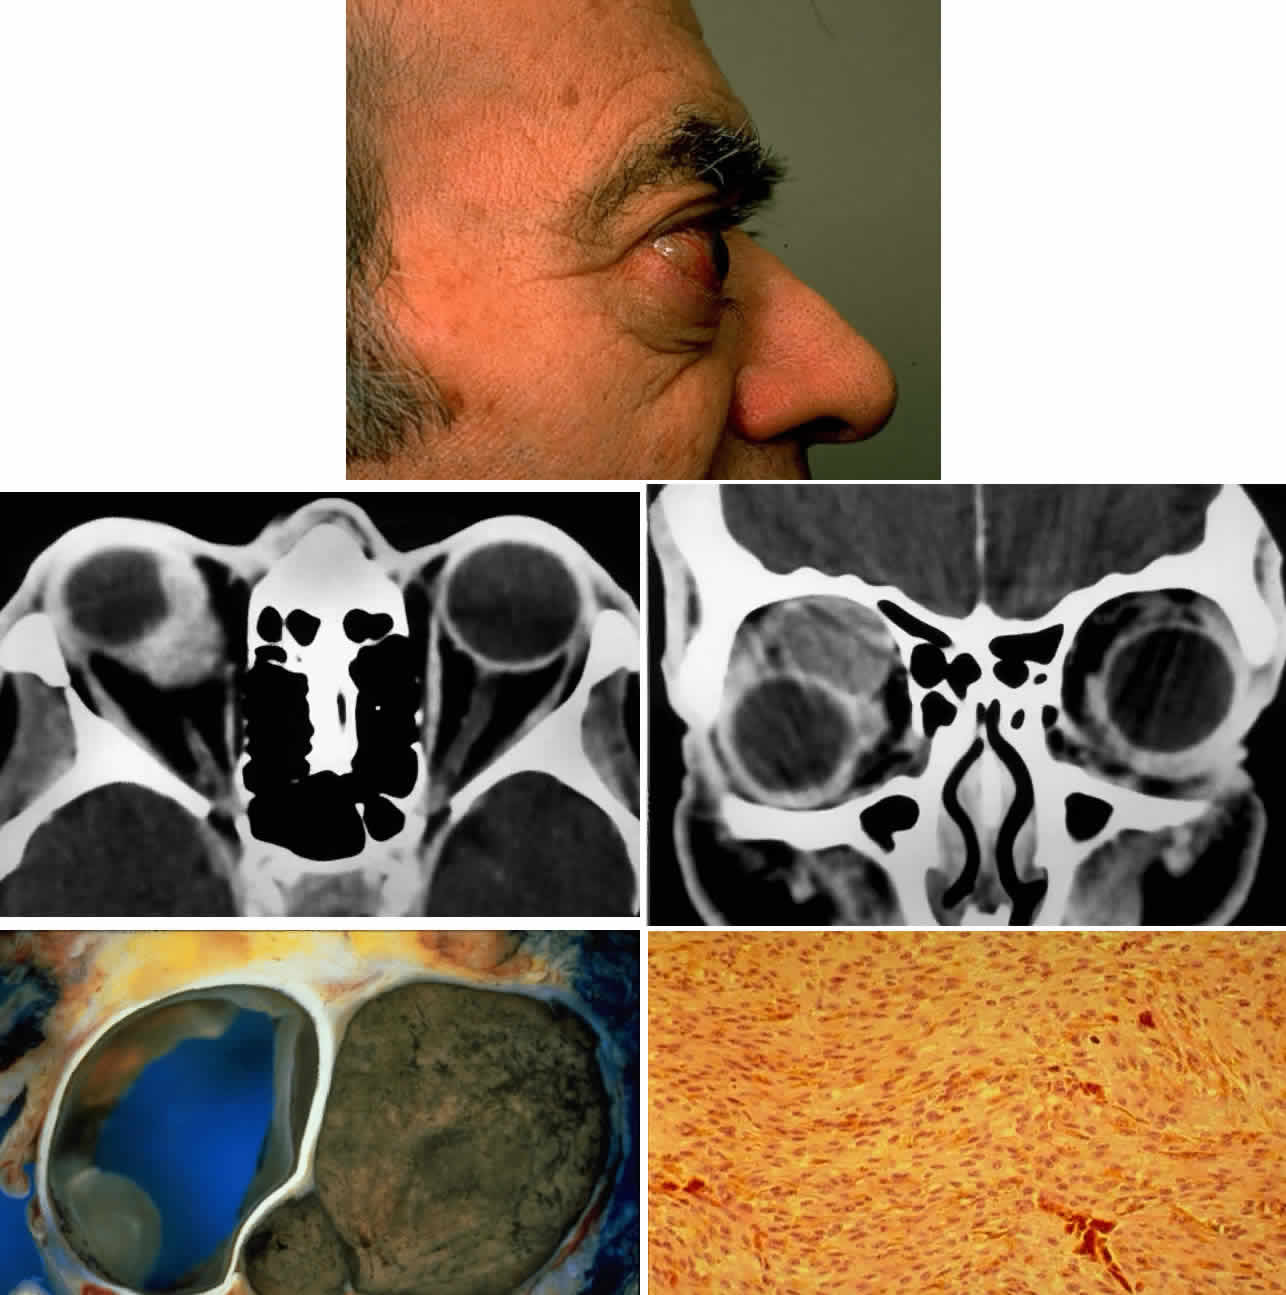

Extrascleral extension occurs in 10% to 15% of patients with uveal melanomas118–120 and may present clinically as a visible anterior nodule, as proptosis in patients with known intraocular tumor (Fig. 13), with phthisis and unsuspected tumor, or as a mass in orbital recurrence. Orbital recurrence associated with hepatic metastasis has been described as late as 42 years after primary enucleation.121 Orbital extension may only become evident at the time of surgery; however, the use of ultrasonography and CT scan may lead to increasing preoperative detection of extrascleral nodules.

Fig. 13. A 65-year-old man presented originally with a right retinal detachment and secondary glaucoma due to a large choroidal melanoma. The patient refused enucleation and self-treated instead with herbal medicines and “health foods.” He presented again 6 years later with acute onset of proptosis associated with pain, periocular edema, erythema, and marked restricted ductions (A). CT scan revealed the intraocular tumor, with massive orbital extension and displacement of the globe anteriorly, downward, and laterally (B and C). He underwent lid-splitting exenteration and split-thickness skin graft from the anterior thigh. The gross specimen shows the massive orbital component of melanoma, which had extended from the posterior choroid through emissarial vessels (D). An area of predominantly spindle-shaped melanoma cells with scattered, heavily pigmented macrophages is shown (E) (H & E, × 200). (D and E courtesy of Valerie A. White, MD, Department of Pathology, University of British Columbia, and the Vancouver Hospital and Health Sciences Center.)

The controversy over the management of orbital recurrence parallels that of intraocular melanoma. It does seem that by the time extrascleral and orbital extension is evident, other biologic factors are already in play that dominate the grave mortality rate, which is 73% to 81% in these circumstances.119,122 The role of exenteration has not yet been defined in a prospective controlled study but there is strong retrospective evidence suggesting that exenteration does not afford protection from metastases, except perhaps in cases of frank transection or nonencapsulation at enucleation.122 Shields and colleagues have summarized their current management (Table 9)123 based on the type of extrascleral extension (flat, nodular, vortex vein, or recurrence after enucleation) and the timing of detection (clinical examination, at surgery, or pathologically after enucleation). Essentially, the trend is toward resection only of adjacent tissues when the lesion is nodular, whereas exenteration (which can usually be subtotal) is reserved for instances where there is evidence of tumor transection at the time of enucleation. In these circumstances, exenteration may be only a palliative measure. The role of preoperative and postoperative radiotherapy has not been clearly determined. Orbital recurrence for similar reasons requires exenteration, although low-grade spindle cell tumors may be curable in such circumstances. The biologic factors previously outlined appear to dominate the poor prognosis in orbital melanoma.